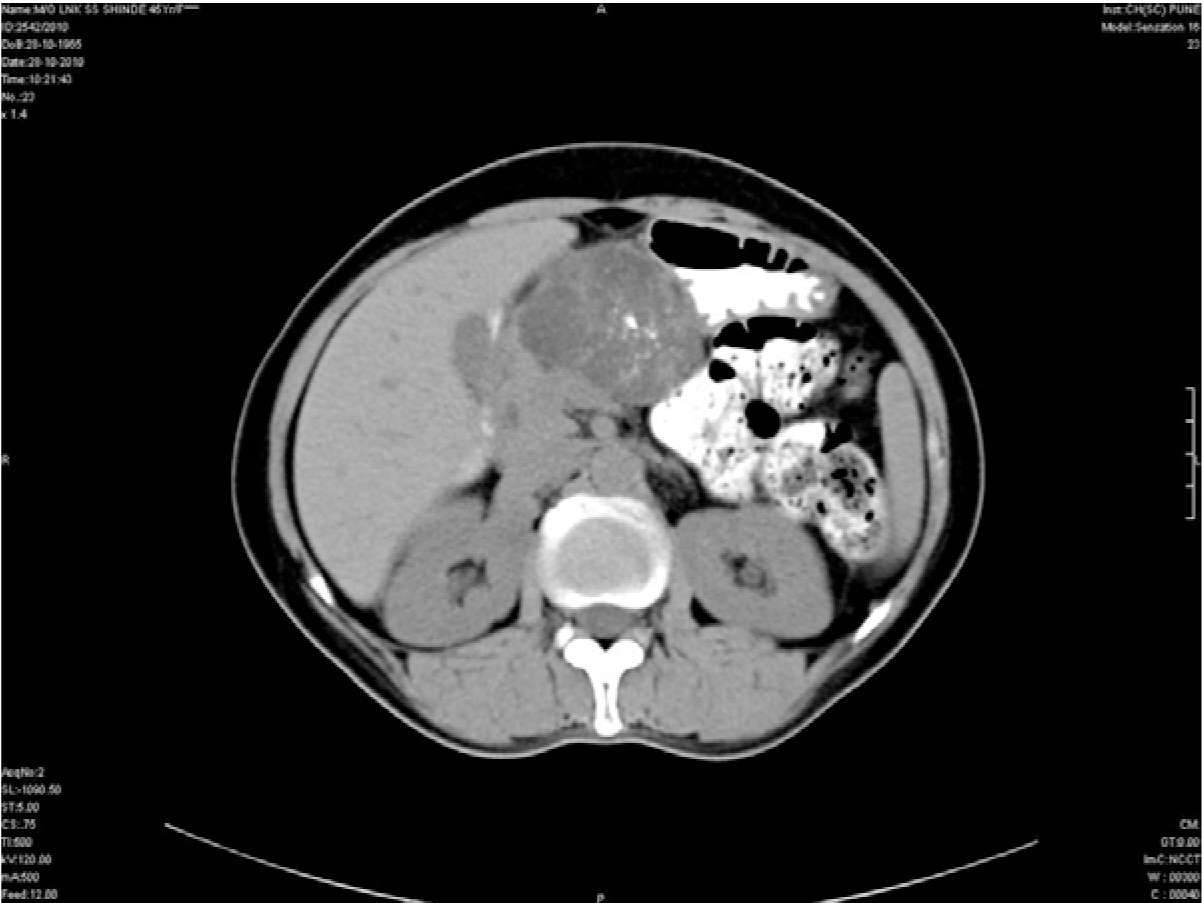

On admission to the hospital, chest and abdominal X-rays were performed which were inconclusive. Routine laboratory studies including hematological and biochemical parameters were normal. Serum amylase was within normal limits. Following this an ultrasound of the abdomen was performed. Ultrasound showed a well-delineated, multi-loculated, cystic lesion of size 5.2x6.2x7.7 cm in the body of the pancreas. The cysts were all subcentimetric giving a honeycomb appearance to the lesion. (Figure 1) Subsequently, a barium meal study was done which showed a smooth extrinsic indentation on the lesser curvature of the stomach. (Figure 2) Contrast-enhanced computed tomography scan showed a large, lobulated, well defined, lesion with multiple subcentimetric non enhancing hypodense cystic areas with enhancing hyperdense walls in the body of pancreas. (Figure 3) Multiple discrete foci of calcifications were seen within the lesion. (Figure 4) Anteriorly the lesion was reaching till anterior abdominal wall, posteriorly it was abutting the splenic vein, superiorly it was abutting the segment IV of liver and inferiorly it was abutting lesser curvature of stomach. After complete investigations, patient was diagnosed as a case of cystic tumor of pancreas and she was operated upon with resection of the lesion. Histology of resected pancreatic tissue revealed multicystic lesion in the body of pancreas containing cysts less than 1 cm in size lined by small flat to cuboidal cells. (Figure 5) There was no architectural or cytological atypia noted. Based on the imaging findings and further confirmation by histopathology a diagnosis of serous cystadenoma of pancreas was made.

Figure 4: Non-contrast computed tomography scan of abdomen showing a multicystic lobulated mass in the body of pancreas with calcifications within the lesion.